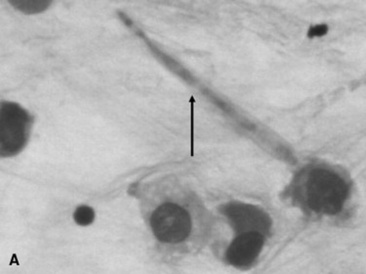

CYTOLOGY

Fungal hyphae may be identified in airway fluid or in impression smears obtained from biopsied masses. Clinicians must be careful in attributing significance to the presence of fungal elements in a TTA. Fungal hyphae are often present either free or in large mononuclear cells in tracheal aspirates from healthy horses.90 A study of healthy thoroughbred racehorses showed that 70% had fungal elements detected in their tracheal aspirates.92 None of the horses from either study had other evidence of fungal pneumonia. Barn fungus such as Alternaria species are nonpathogenic and rarely incite an inflammatory response in the host. The organisms often have a blocklike appearance and may be colored (Fig. 31-18, A and B). A normal predominance of macrophages, lymphocytes, and nondegenerate neutrophils (<5% to 10%) would be expected.

Fig. 31-18 Alternaria species from transtracheal wash specimens obtained from healthy horses. A, An extracellular spore (arrow) with several macrophages, squamous cell (indicative of pharyngeal contamination. B, Intracellular spores (arrow) within binucleated macrophage.

Courtesy Elizabeth Welles, Auburn University, Ala.

To be significant cytologically, large numbers of fungi should be involved in the inflammatory process within the lung. With fungal pneumonia, aspirates may contain predominately neutrophils that often are degenerate and may contain intracellular fungal hyphae. If processing of the sample is delayed, extracellular fungi may be phagocytized, which confuses the interpretation. Some fungi have characteristic morphologic features that can permit an early presumptive identification (Table 31-5).